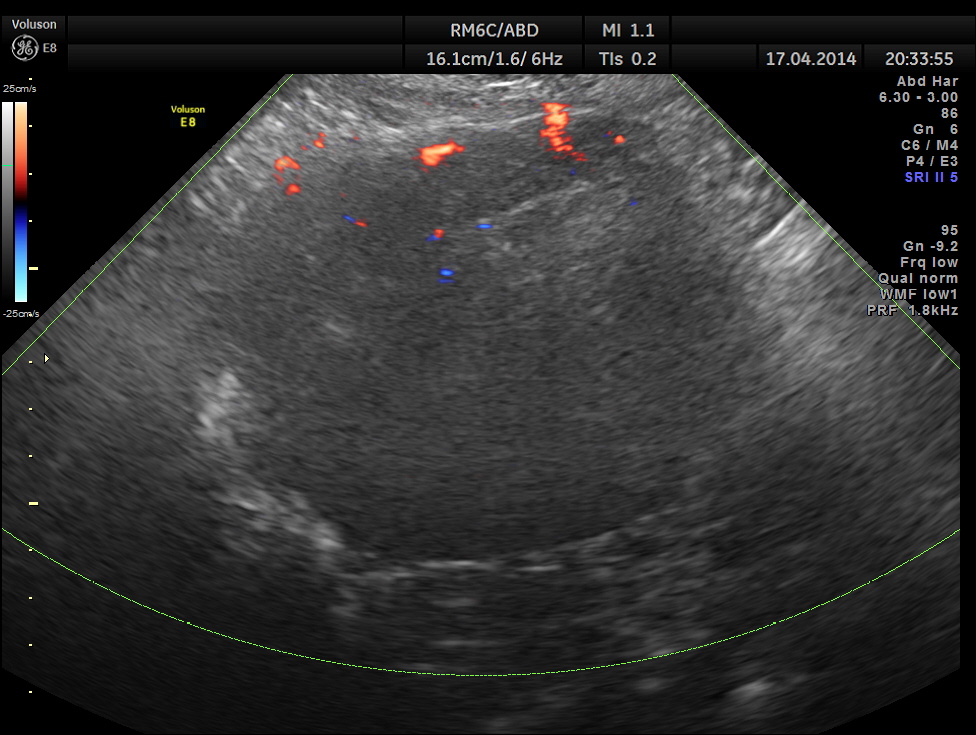

Two distinct mass lesions were seen in the right side of the abdomen in the lumbar and hypochondriac regions . Though they appeared distinct from the liver , it was a bit confusing.

Thw two masses seen out of the uterus and mainly in the right upper quadrant are shown below.

The ultrasound gave us a few inconclusive findings . Uterus was massively enlarged ; a large fibroid was seen ; adenomyosis was seen ; endometrium was thickened ; two large mass lesions were seen in the right upper quadrant and right lumbar region . But it was difficult to ascertain the origin of these extra uterine masses .